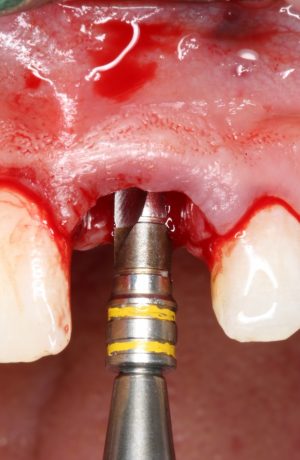

Прежде, чем приступить к аугментации (пластике) лунок зубов, мы подготовили лунки для имплантатов. В таких клинических случаях нет необходимости в использовании шаблона. Вместо этого, мы применяем общепринятые правила позиционирования и соблюдаем рекомендации производителя по хирургическому протоколу:

В процессе ирригации лунки промываются, что позволило нам еще раз подтвердить ранее сделанные выводы. С помощью аналогов имплантатов, входящих в хирургический набор Xive, мы проверили возможность стабилизации имплантатов в будущих лунках. Исходя из правил подбора и позиционирования имплантатов (я очень рекомендую почитать об этом здесь>>) мы остановились на Xive S диаметром 3,4 мм и длиной 13 мм.

Подготовка двух лунок для имплантатов занимает около 10 минут.